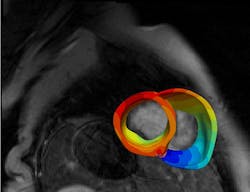

In their study, the researchers created digital three-dimensional models of the hearts of 45 CS patients treated at the Johns Hopkins Hospital. To do this, they took the novel approach of combining data from two different kinds of heart scans: contrast-enhanced cardiac MRIs, which detect fibrosis, or scarring, and PET scans, which detect inflammation. The team used computer simulations to apply a series of electrical signals at various locations throughout each of the models and gathered millions of data points measuring each heart’s reaction.

Lastly, the team compared their simulations against scans of lesions in the hearts of the patients who had subsequently undergone a procedure to reset their heartbeats, finding that their predictions were consistent with actual outcomes.